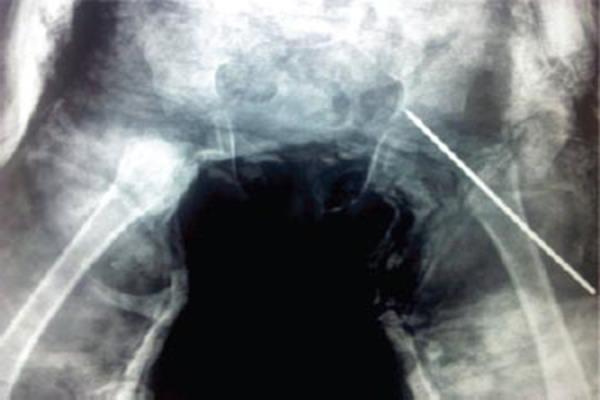

Complete Traumatic Separation of Proximal Femoral Epiphysis in A 2 Year Old Child.

Hip fractures are very common in adults, but are rare in children, comprising less than 1% of all pediatric fractures. Separation of the proximal femoral epiphysis can occur in a child with a traumatic hip dislocation and an open epiphysis. Regardless of the mechanism of proximal femoral epiphyseal separation, the prognosis is poor secondary to the development of osteonecrosis.

CASE REPORT

Here we are reporting a case of complete separation of the proximal epiphysis of the femur in a 2 year old female child. She was treated by open reduction and internal fixation by a single k-wire of proximal femoral epiphysis. Regular follow up showed fusion of proximal femoral epiphysis at about 3 months of post operative period. After 8 months of follow up she can stand and walk without support. Long term outcome is awaited.

Traumatic separation of the proximal femoral epiphysis is a rare but devastating injury because osteonecrosis occurs in most cases. In our study we found fusion of the proximal femoral epiphysis to the neck after 3 months of postoperative period. But to comment upon the final outcome a long follow up is awaited.